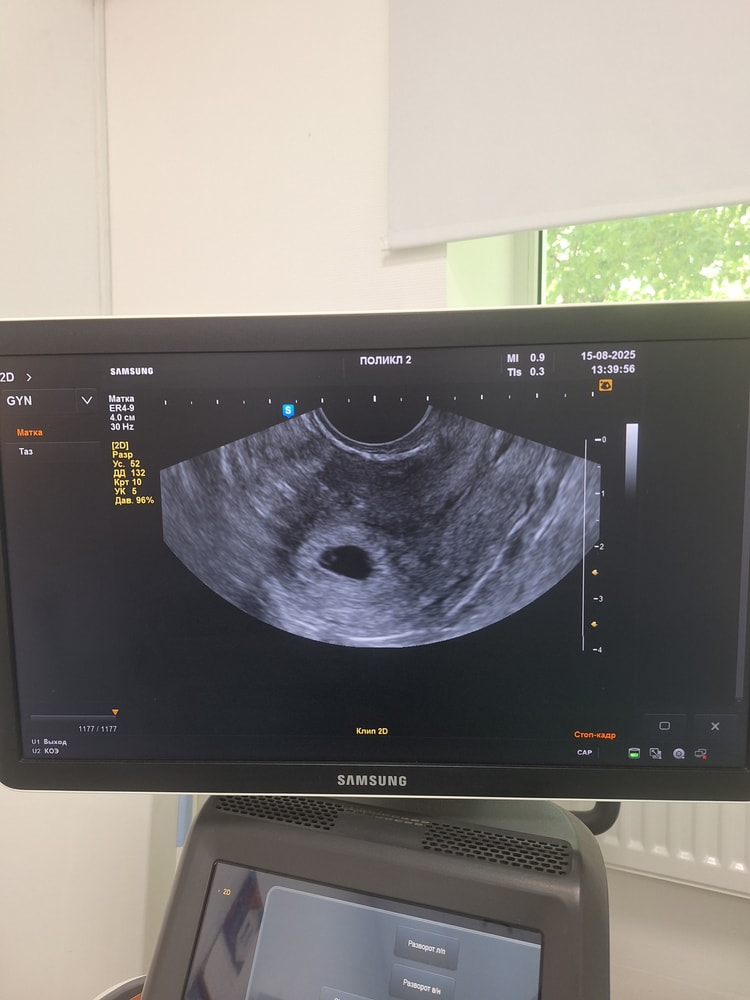

И тут врач очень удивленным голосом говорит "ааа, вот оно! Плодное яйцо в матке 11 мм, миометрий в тонусе, больше пока не вижу ничего, завтра на трансвагинальном УЗИ уже наверное увидите ЖМ".

P. S. А вот и УЗИ на 18 дпп, получается. Гематом и отслоек нет 🙏